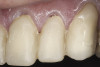

(12.) Preoperative right anterior, close-up view.

Figure 12

(13.) Preoperative anterior, close-up view.

Figure 13

(14.) Preoperative left anterior, close-up view.

Figure 14